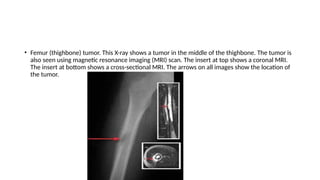

• Femur (thighbone) tumor. This X-ray shows a tumor in the middle of the thighbone. The tumor is

also seen using magnetic resonance imaging (MRI) scan. The insert at top shows a coronal MRI.

The insert at bottom shows a cross-sectional MRI. The arrows on all images show the location of

the tumor.